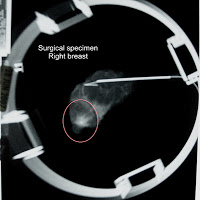

October is breast cancer awareness month. And I am a breast cancer survivor. My journey began when I was 47 and had a screening mammogram that showed a lesion in my right breast. Today I had my first oncology appointment with this 12 year old oncologist who looks like Doogie Howser’s little sister. They have the rest of my path report back. My hormone receptors were negative.That means I can’t take tomoxofin. I can’t do the hormone therapy in conjunction with the radiation. What that means is, my ass is going to be bald…okay, maybe not my ass, but possibly my head! I’m going to have to have chemo! That little tiny, less than 1cm tumor was an aggressive little bastard with high proliferation margins and no hormone receptors, so if I want to decrease my chances of a relapse ten years down the road, then I’m going to have to take chemo.

Another lingering threat. The radiation oncologist didn’t like the results of my second excision biopsy. The medical oncologist believed chemo would destroy any remaining DCIS in the breast and did not think it was a problem. Apparently, my radiation oncologist didn’t agree. In the frozen slides from the second biopsy, there was DCIS in five of eight slides less than 1 mm from the surgical margin. There was only one DCIS on one slide in the original surgery. There shouldn’t have been any DCIS in the second biopsy. The possibility existed that my breast was potentially riddled with DCIS. And doctors usually recommend a mastectomy in a case like that.

I’d already had chemo to destroy any remaining DCIS in the breast. Lots of women have DCIS and never develop breast cancer, and I didn’t want mastectomy to be a knee jerk reaction to fear. The pathology report said DCIS in five of eight specimens but the oncologist didn’t know if it was a speck or a boat load.